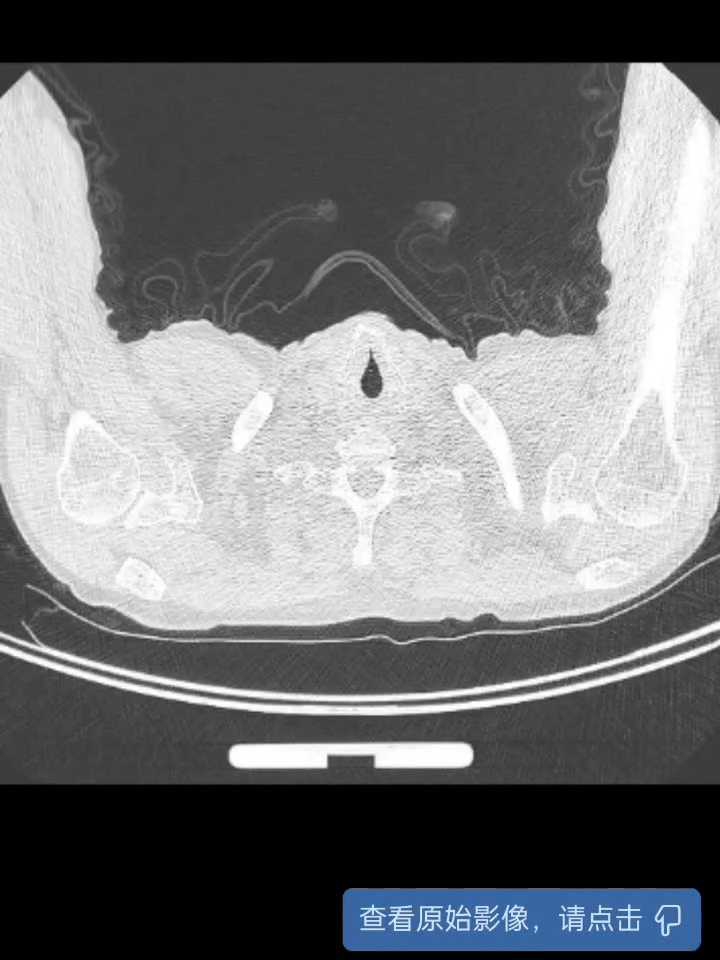

术前胸部CT提示考虑双肺结核可疑,后转入呼吸科进一步检查。